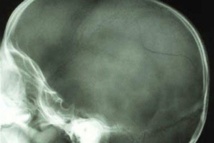

HUAHINE, mardi 26 février 2013. Un jeune homme de 17 ans a été opéré dimanche au Centre hospitalier du Taaone d’une fracture de la voûte du crâne après avoir été agressé par un jeune homme de 20 ans, en état d’ivresse. Les faits se sont déroulés samedi (le 23 février) vers 18h30 à Huahine. L’agresseur a porté des coups à sa victime, le fait tomber au sol et lui fracasse le crâne avec un pot de fleurs.